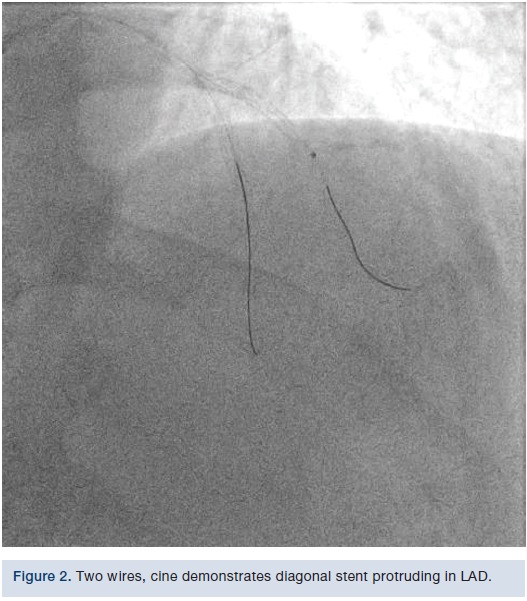

We used a 6 French Extra Backup (EBU) 3.5 guide (Medtronic). We initially put a Runthrough wire (Terumo) down the diagonal and a Samurai wire (Boston Scientific) down the LAD. We then took a 0.9 laser after bivalirudin was administered and tried to cross into the diagonal; however, there was wire bias. The wire was pulled from the LAD into the diagonal, the laser was placed across the ostium, and then we rewired the LAD. Laser atherectomy was performed at a setting of 60/40, debulking the in-stent restenosis. We were then able to deliver a 2.5 x 10 mm AngioSculpt (Spectranetics), predilated, and placed a 2.5 x 24 mm Synergy drug-eluting stent (Boston Scientific) at 12 atmospheres. We post dilated with a 2.75 NC balloon (Medtronic), staying short of the ostium, because there was concern about where the stent was located. However, once we post dilated the stent, TIMI-3 flow was visible in both vessels. There was disease beyond the stent that was possibly wire spasm, but plaque shift in the LAD was visible as well, and on magnified views, it appeared that the struts might have been hanging out in the LAD, which would be why, when we manipulated the devices into the diagonal, some plaque shift took place in the LAD. There now appeared to be a 90% stenosis in the LAD focal right afterwards. Nitroglycerin was given and it did not resolve; therefore, we elected to go ahead and fix it. A Runthrough wire was put down the LAD and then a 2.75 x 12 mm noncompliant balloon that was used in the diagonal was dilated in the LAD. We crushed the ostium with the diagonal stent, and were then able to deliver a 3.0 x 16 mm stent going across the diagonal and overlapping with the previous LAD stent. The stent was deployed at 14 atmospheres. The LAD was rewired with the Runthrough wire and the Samurai wire pulled back. The diagonal was wired with the Samurai wire and now both wires were crossed. A 2.0 mm compliant balloon in the diagonal was dilated to 14 atmospheres, opening up the struts. A 3.0 x 12 mm noncompliant balloon was placed in the LAD and a 2.5 x 15 mm compliant balloon was placed in the diagonal. Nominal inflations were performed in both vessels, in a kissing manner. Final angiography revealed TIMI-3 flow without dissection, perforation, or embolization. The wires were removed. Orthogonal views were obtained, revealing TIMI-3 flow without dissection, perforation, or embolization. The patient tolerated the procedure well. The guide was removed and a TR Band (Terumo) was placed over the radial artery.Discussion